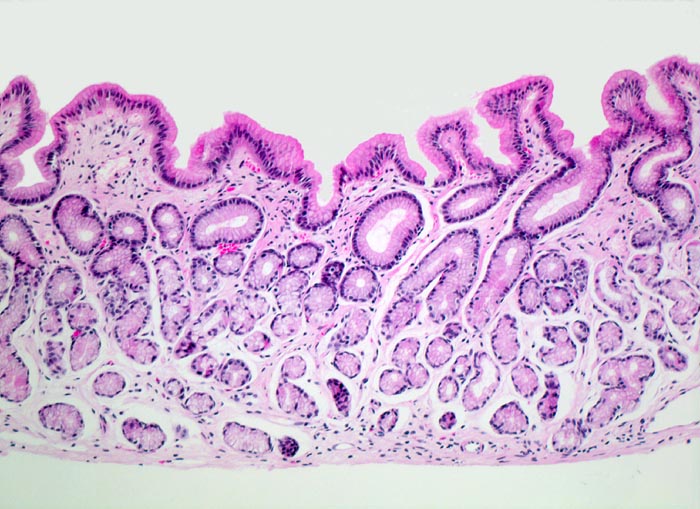

normales Magenantrum

Magenantrum

Die Foveolae im Magenantrum sind tiefer als im Corpus (bis zu 50% der gesamten Mukosabreite). Die pylorischen Schleimdrüsen sind ausgekleidet durch hochprismatische Zellen mit hellem Zytoplasma. Die Lamina propria ist weitgehend frei von Entzündungszellen.